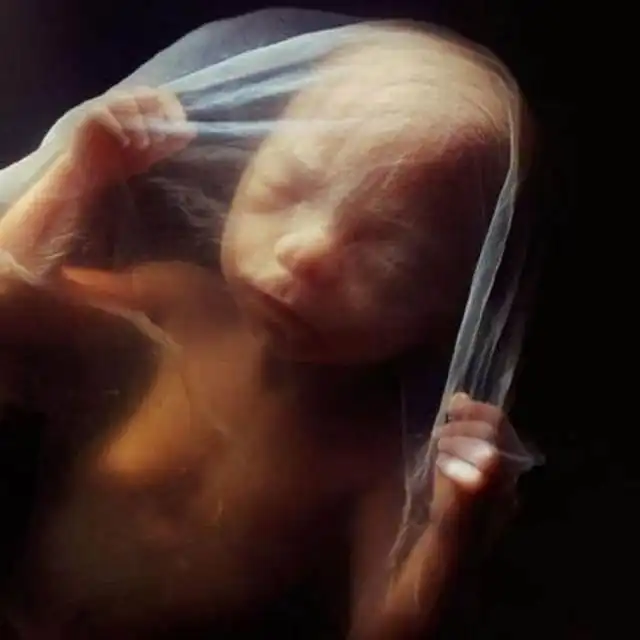

Восемь недель. Быстрорастущий эмбрион хорошо защищен во чреве матери. С помощью электронного микроскопа Нильссон смог увеличить изображение в сотни тысяч раз.

10 недель. Веки уже полуоткрыты. В течение нескольких дней они сформируются полностью.